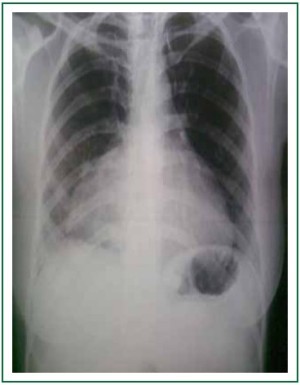

A 28 years old newly married lady during her routine medical health check up before leaving to Middle east was found to have right paracardiac shadow in her chest X-ray (Figure 1). She had no complains of breathlessness, abdominal pain, nausea, vomiting, loss of appetite or weight and bowel/bladder disturbances. She had regular menstrual cycle. A physical examination revealed a firm mobile non tender swelling in the hypo gastric region.

Figure 1. Chest X-ray showing right para cardiac shadow.